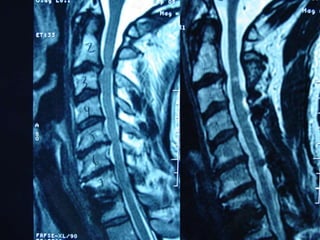

77 year old woman with h/o hand weakness/numbness/ataxia

Prior acdf 14 years ago

Note:the black line directly posterior to the vertebral bodies and relative

Thinning of spinal cord, note normal disc height